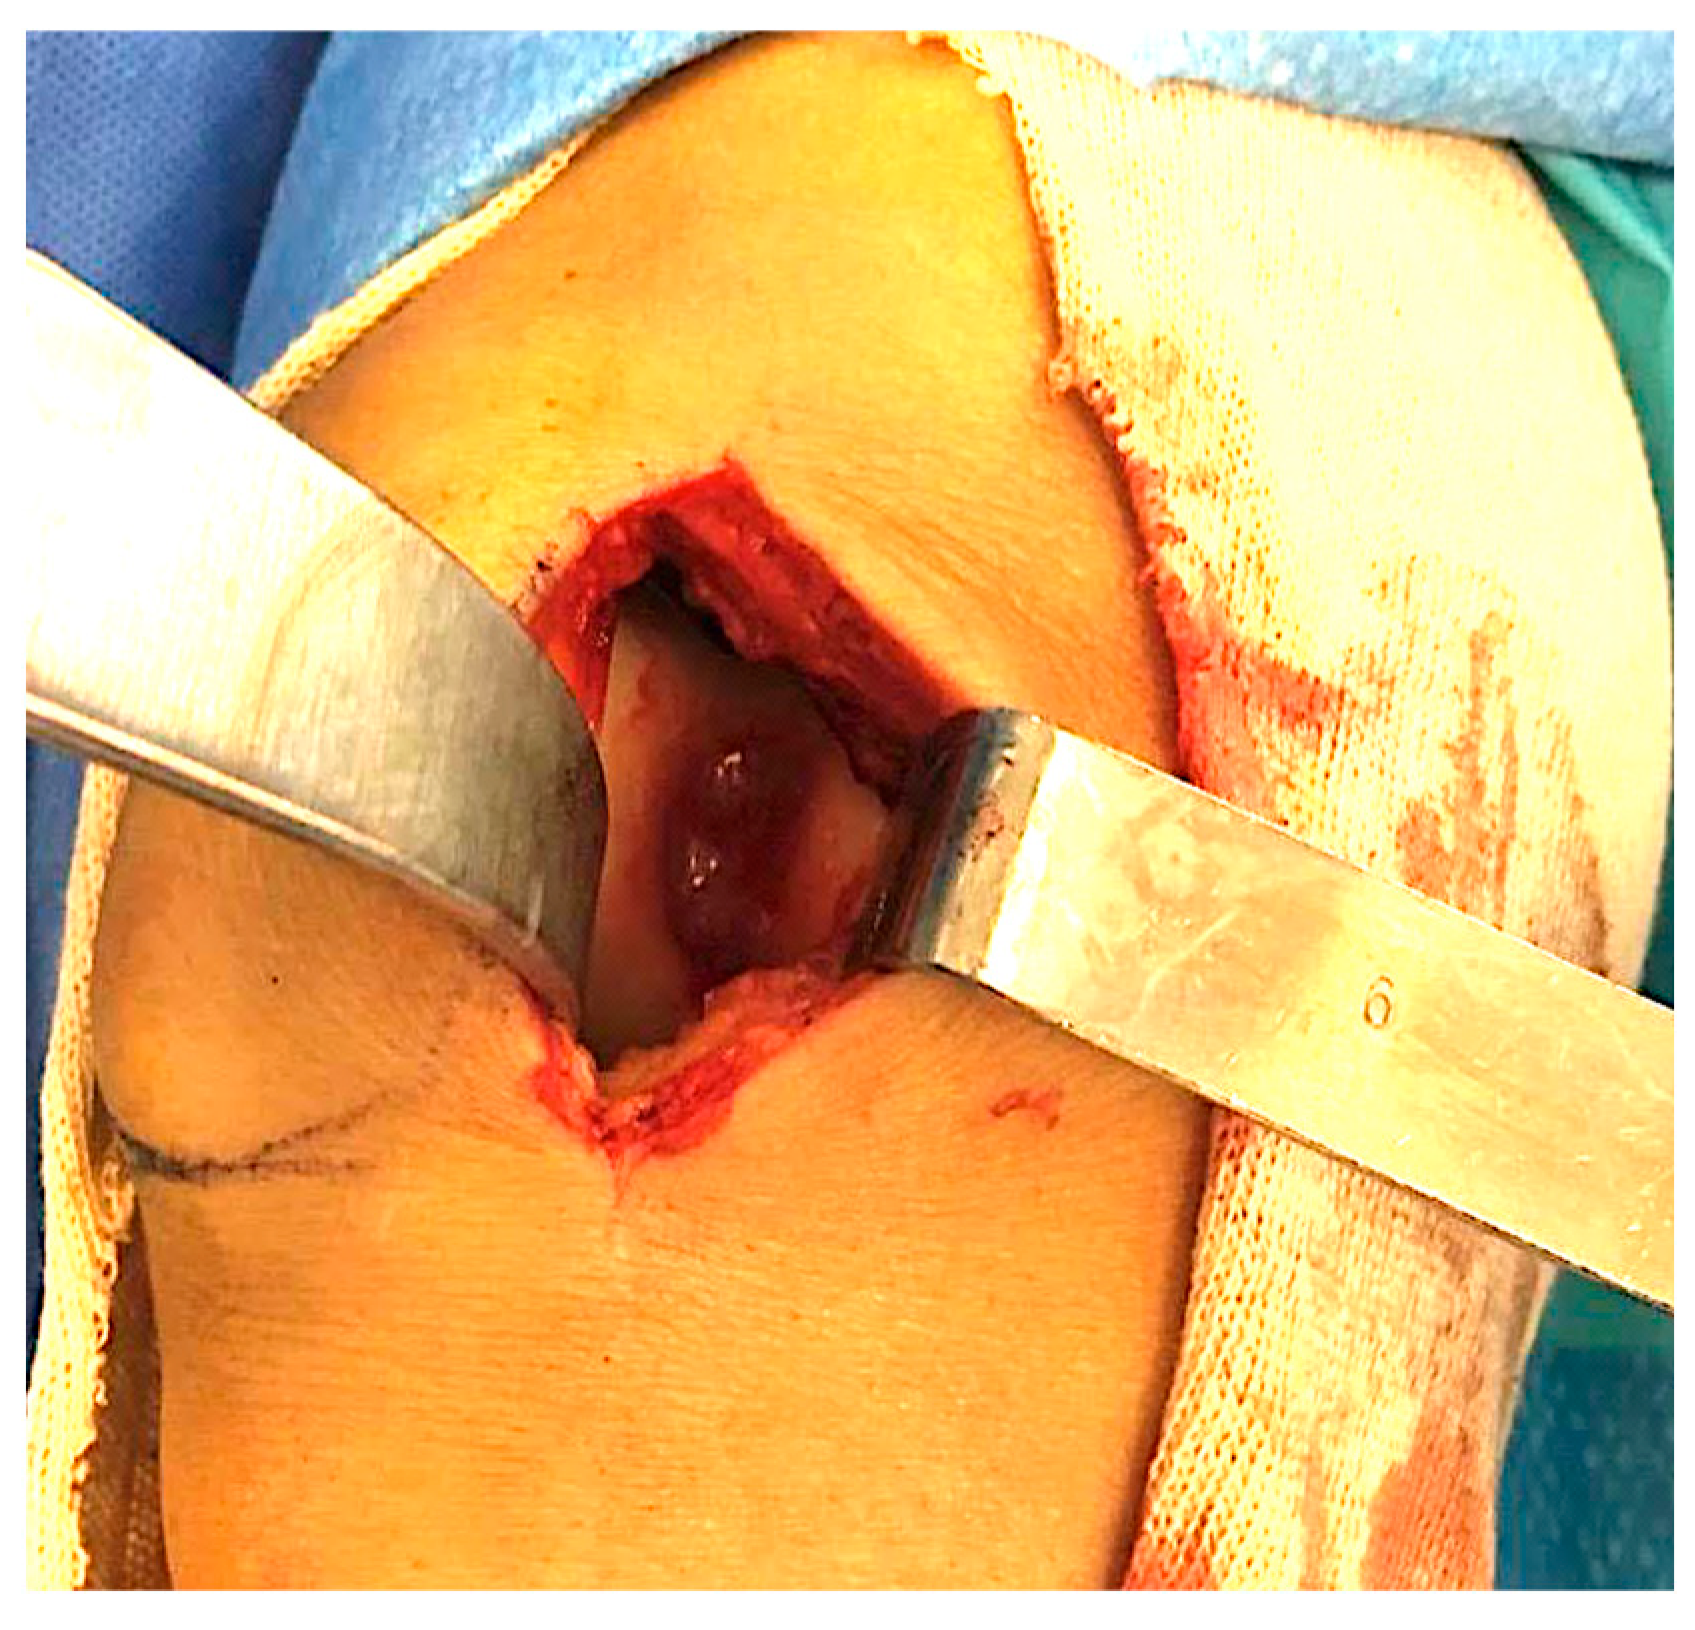

2.1. Surgical Procedure